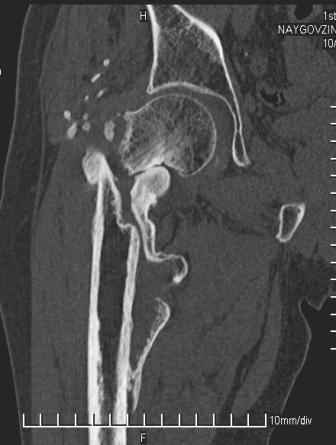

Больной Н. 44 года травма 1,5 года назад июнь 2008 года чрез-под вертельный перелом правого бедра. Во время лечения у больного развился алк. делирий, проводилось консервативное лечение перелома.

Беспокоят боли, укорочение конечности.Укорочение 3 см. Ногу поднимает, сгибание ограничено, ротационные движения в полном объеме.На КТ перелом сросся за счет костной мозоли.Что делать?

Уважаемый Глеб, боли из-за ложного сустава шейки бедра. Сращения там нет.

Уважаемый Глеб! Укорочение наверное побольше, да и наружно-ротационная установка скорее всего присутствует. Суставная щель прекрасная, головка живее всех живых. Ратую за подвертельную с латерализацией: исключает нарушение механической оси («исключает вальгус в коленe»), максимально удлиняет без натяжения m.iliacus. Для иллюстрации остеотомия-переделка (слава богу не автопеределка) у мужчины 65 лет.